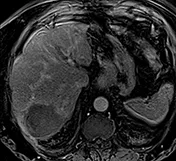

La cicatrice de thermoablation se présente sous forme d’une image nodulaire avasculaire, spontanément hyper intense T1 avant injection, en rapport avec la nécrose de coagulation (figure 2).

Une récidivé loco-régionale se présente sous forme de prise de contraste nodulaire sur les berges de cette cicatrice. Les séquences en pondération T2 ou en diffusion pour diagnostiquer la récidive sont plus difficiles à interpréter car il persiste longtemps après le geste une hyper intensité T2 au sein ou au pourtour de la cicatrice.

| Contrôle en IRM après radiofréquence multibipolaire : la cicatrice de thermoablation apporte des marges centimétriques, est totalement avasculaire aux différents temps de l’injection (artériel et portal). | |